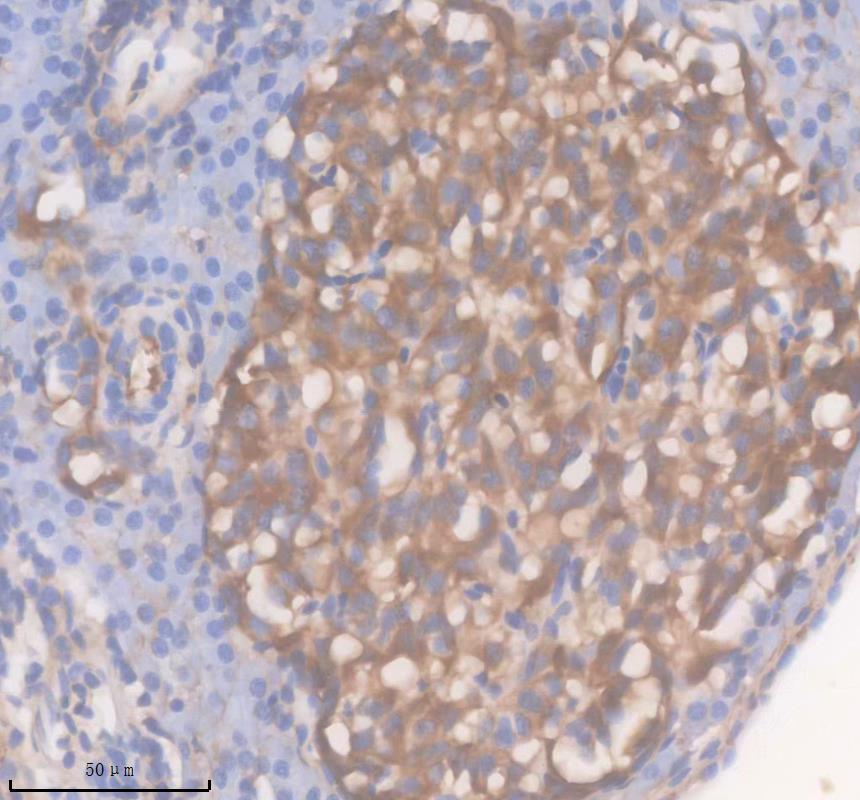

• IHC analysis of Anp32e using anti-Anp32e antibody (DZ41646) .

Anp32e was detected in a paraffin-embedded section of zebrafish intestines tissue. The tissue section was incubated with rabbit anti-Anp32e Antibody (DZ41646) at a dilution of 1:200 and developed using HRP Conjugated Rabbit IgG Super Vision Assay Kit (Catalog # SV0002) with DAB (Catalog # AR1027) as the chromogen.